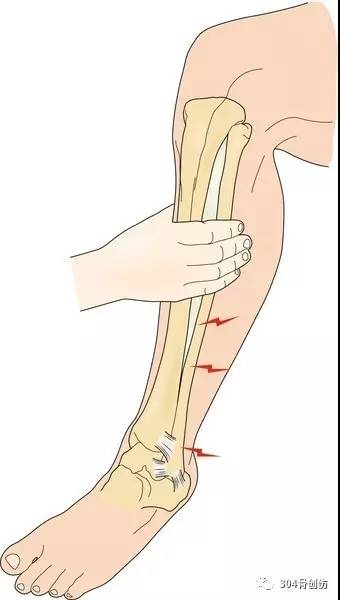

临床检查

踝关节骨折应根据骨折类型,甄别有无下胫腓联合损伤可能,无骨折踝关节损伤应详细询问受伤机制,仔细局部检查,防止漏诊下胫腓联合损伤。下列检查有助于诊断。多种体格检查相结合,提高诊断率。

外旋试验

膝关节及踝关节屈曲90°,足部外旋

诱发胫腓联合疼痛

挤压试验

挤压胫骨和腓骨近端

交叉腿

试验

患者坐位,将损伤脚交叉放置于健侧患肢上,在损伤侧膝关节向下施加轻度压力

用力

背伸试验

踝关节背伸,而后挤压胫腓骨远端

胫腓联合疼痛减弱

足外旋试验

(Kleiger test)

胫腓骨横向挤压试验

(Hopkinson squeeze test)

交叉腿试验

(Crossed-leg test)

用力背伸试验

Forced dorsiflexion test